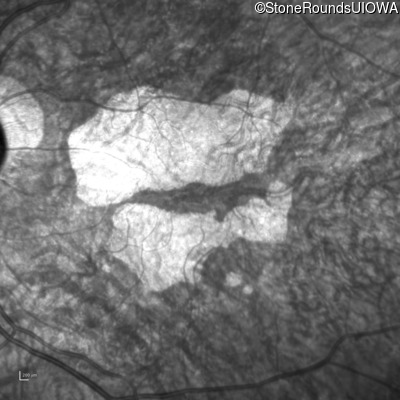

Infrared Fundus Photograph - Right - 10/140

Exemplar